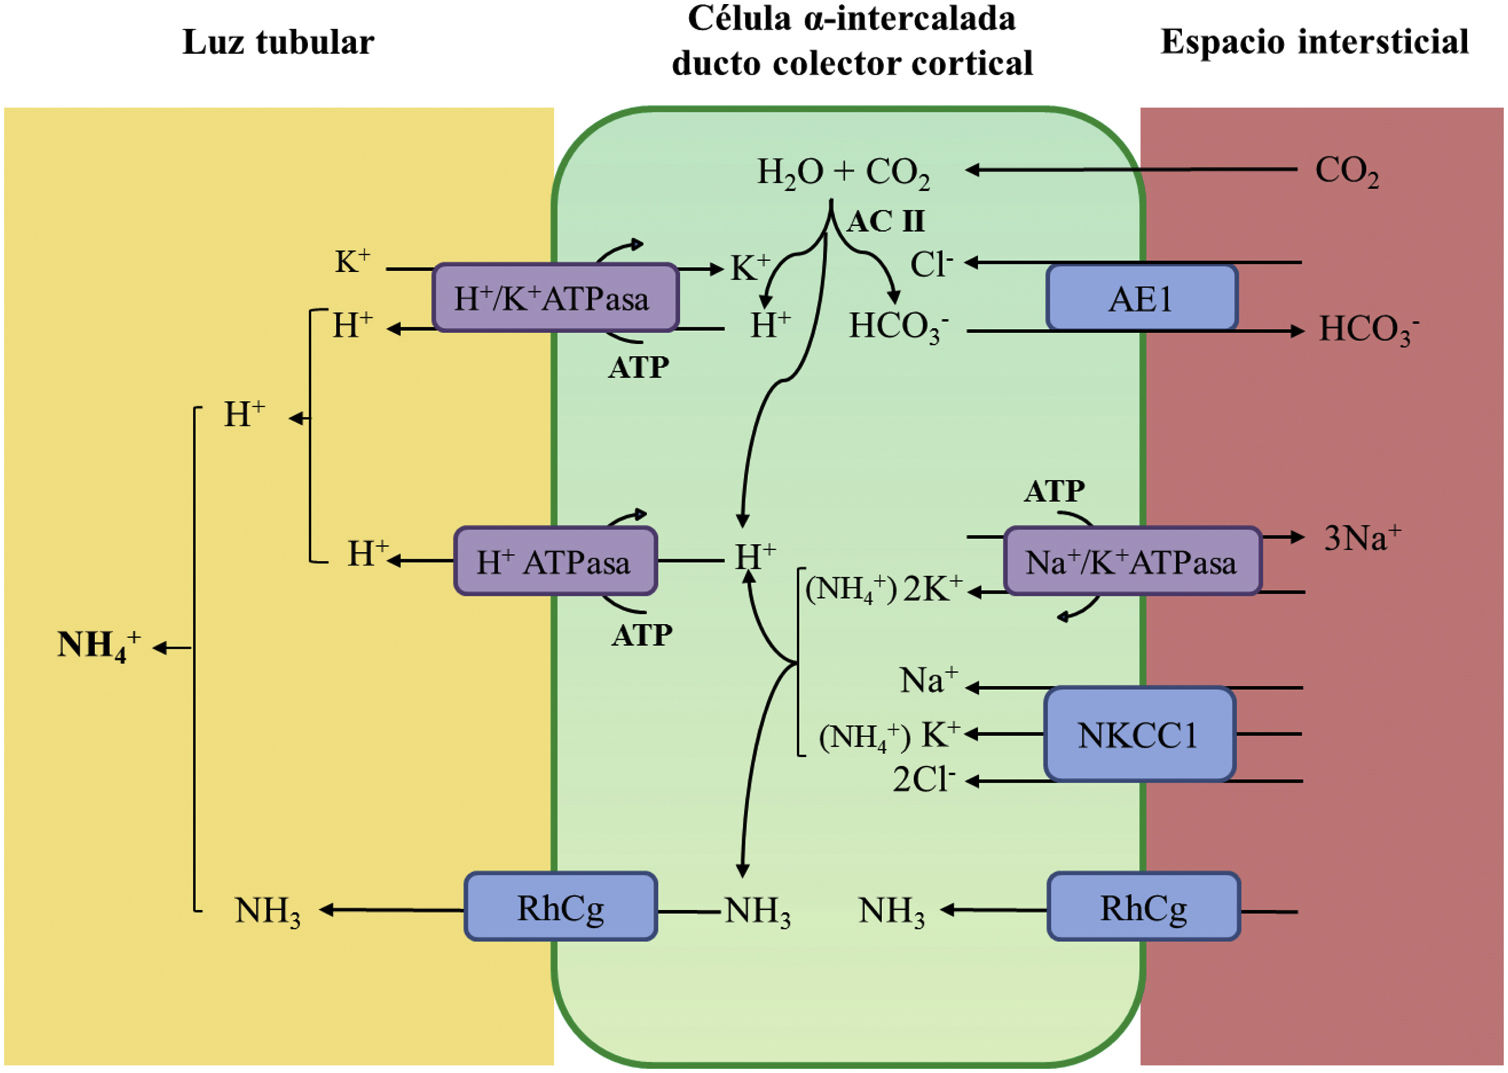

La acidificación tubular distal de la orina en condiciones fisiológicas se resume en la figura 1. La H+-ATPasa (V-ATPasa) es una bomba de protones altamente conservada que se expresa en las células α-intercaladas y que está formada por dos dominios, V1 y V0. Los defectos en la actividad de la bomba H+-ATPasa causan la mayoría de los casos primarios de ATRd de herencia autosómica recesiva. Son debidos a mutaciones en los genes ATP6V1B1,ATP6V0A4 (tabla 1) que codifican las subunidades B1y A4 de la bomba H+ ATPasa, respectivamente4–6. La ATRd de herencia autosómica recesiva asociada a sordera puede ser producida por mutaciones en el gen FOXI 1 que codifica un factor de transcripción que es necesario para la expresión de al menos 4 subunidades de la H+-ATPasa (A1, B1, E2 y a4)7. Un cuarto gen, WDR72 (OMIM 613211), cuando está mutado produce otra variedad de ATRd autosómica recesiva; este gen parece estar implicado en el tráfico intracelular de proteínas reguladoras del equilibrio ácido-base provocando su retención intracelular o un direccionamiento erróneo8,9. Con relación a las manifestaciones extrarrenales: 1) los pacientes con ATRd recesiva causada por mutaciones en los genes ATP6V1B1, ATP6V0A4 pueden presentar una sordera de percepción de manera frecuente y constante en las mutaciones del gen FOXI 1, siendo de inicio temprano y asociado al síndrome de Pendred (ORPHA:705)8, y 2) los pacientes con ATRd recesiva causada por mutaciones del gen WDR72 pueden presentar una amelogénesis imperfecta.

Acidificación de la orina distal en condiciones fisiológicas. La acidificación de la orina tiene lugar en los túbulos distal y colector a través de 3 procesos relacionados: a) reabsorción de la cantidad residual de bicarbonato (10%), que no ha sido recuperada en zonas más proximales de la nefrona; b) titulación del anión fosfato divalente (HPO42−) con H+ que se transforma en anión fosfato monovalente (H2PO4−) o acidez titulable; c) acumulación de amoniaco (NH3) intraluminal que capta H+ y forma amonio (NH4+). La secreción de H+ y la titulación de los tampones urinarios da lugar a la acidificación de la orina con lo que se pueden alcanzar valores de pH cercanos a 4,5 en condiciones de estimulación máxima del proceso. Este hecho se realiza en las células α-intercaladas que se localizan en el túbulo contorneado distal tardío, el túbulo conector y en los ductos colectores corticales y medulares.

La secreción distal de H+ genera una cantidad equimolar de bicarbonato. Por cada molécula de hidrogeno que se excreta a la luz tubular, se genera intracelularmente una molécula nueva de bicarbonato gracias a la acción de la anhidrasa carbónica intracitoplásmica (AC tipo II), que es transferida a la sangre mediante el intercambiador de aniones Cl−-HCO3− (AE1). Las células α-intercaladas secretan H+ por medio de la ATPasa vacuolar (H+-ATPasa) que transfiere H+ activamente a través de la membrana luminal y la H+-K+-ATPasa que intercambia H+ por potasio. La función de la H+-ATPasa está marcadamente influenciada por la electronegatividad generada en la luz tubular por el transporte simultáneo de Na+ en las células principales del ducto colector. La acumulación de NH3/NH4+ en la médula genera un gradiente de concentración que favorece su entrada por la membrana basolateral de las células intercaladas-α. La excreción de NH3/NH4+ requiere de al menos 2 pasos, a saber, ingreso basolateral y excreción luminal. La captación desde el intersticio del NH3/NH4+ se lleva a cabo por varias vías que incluyen el transportador Na+/K+/2Cl− (NKCC1), la Na+-K+-ATPasa (en el caso de estos dos trasportadores, el NH4+ puede ser transportado en lugar de potasio), los canales de gases Rhcg (human Rhesus C glycoprotein) y los canales de NH4+ activados por hiperpolarización HCN (hyperpolarization-activated cyclic nucleotide-gated cationic non-selective). La membrana luminal tiene una alta permeabilidad para NH3. Los canales RhCG están presentes en la membrana luminal y en la membrana basolateral.

En el lado basolateral solo se ha descrito un tipo de ATRd de herencia autosómico dominante (tabla 1) en la mayoría de los casos, que está producido por mutaciones en el gen SLC4A1 (OMIM 109270) que codifica las 2 isoformas del intercambiador de aniones Cl−-HCO3, la isoforma renal también conocida como kAE1 (kidneyanion exchanger 1) y la isoforma de los hematíes también conocida como proteína banda 3 (erythroid isoform o eAE1); kAE1 es responsable de la reabsorción de HCO3− junto con la excreción de Cl− en las células α-intercaladas10 (fig. 1). Este tipo de ATRd, se ha asociado a formas de presentación clínica menos graves, con inicio tardío en la infancia, adolescencia y en pacientes adultos, con menor impacto en el crecimiento comparado con las formas de herencia autosómico recesiva8.

¿Qué ocurre cuando el defecto genético repercute en la actividad del intercambiador de aniones Cl−-HCO3− como es lo que le acontece a nuestros pacientes? El bicarbonato, formado intracelularmente por la acción de la anhidrasa carbónica no puede abandonar la célula a través de la membrana basolateral por lo que se eleva el pH intracelular que va a inhibir la actividad de la H+-ATPasa. Por ello, los pacientes con ATRd autosómica dominante tienen orinas con un pH superior a 6 en situación de acidosis espontánea20 o en las pruebas de acidificación realizadas con estímulo de H+ como en las efectuadas con NH4CL20,21. La falta de intercambio con Cl− explica la hipercloremia propia de la ATRd (fig. 1).